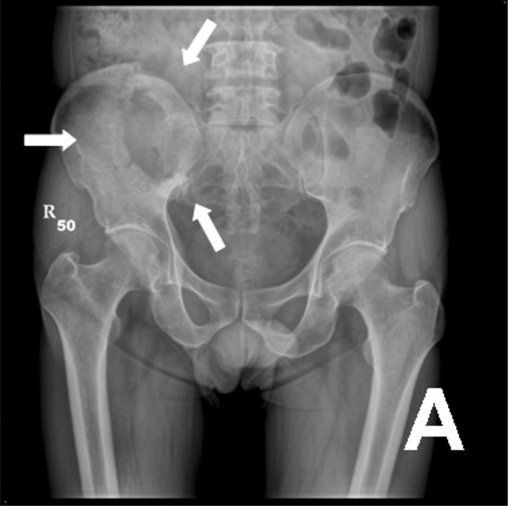

Large osteolytic lesion over iliac (white arrows). Image source: Kuebi, Wikimedia Commons.